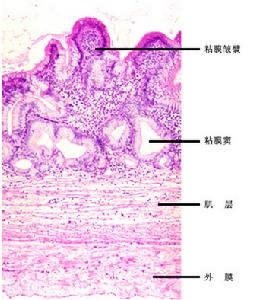

膽囊管綜合徵病理圖症狀體徵

膽囊管綜合徵者開腹手術中常可見到膽囊增大,並有一定程度擴張,手指按壓膽囊後膽汁不能排空。其膽囊本身可無異常,膽囊管組織病理檢查常常見到輕度到中度的炎性改變,管壁增厚或有較典型的增生性改變。